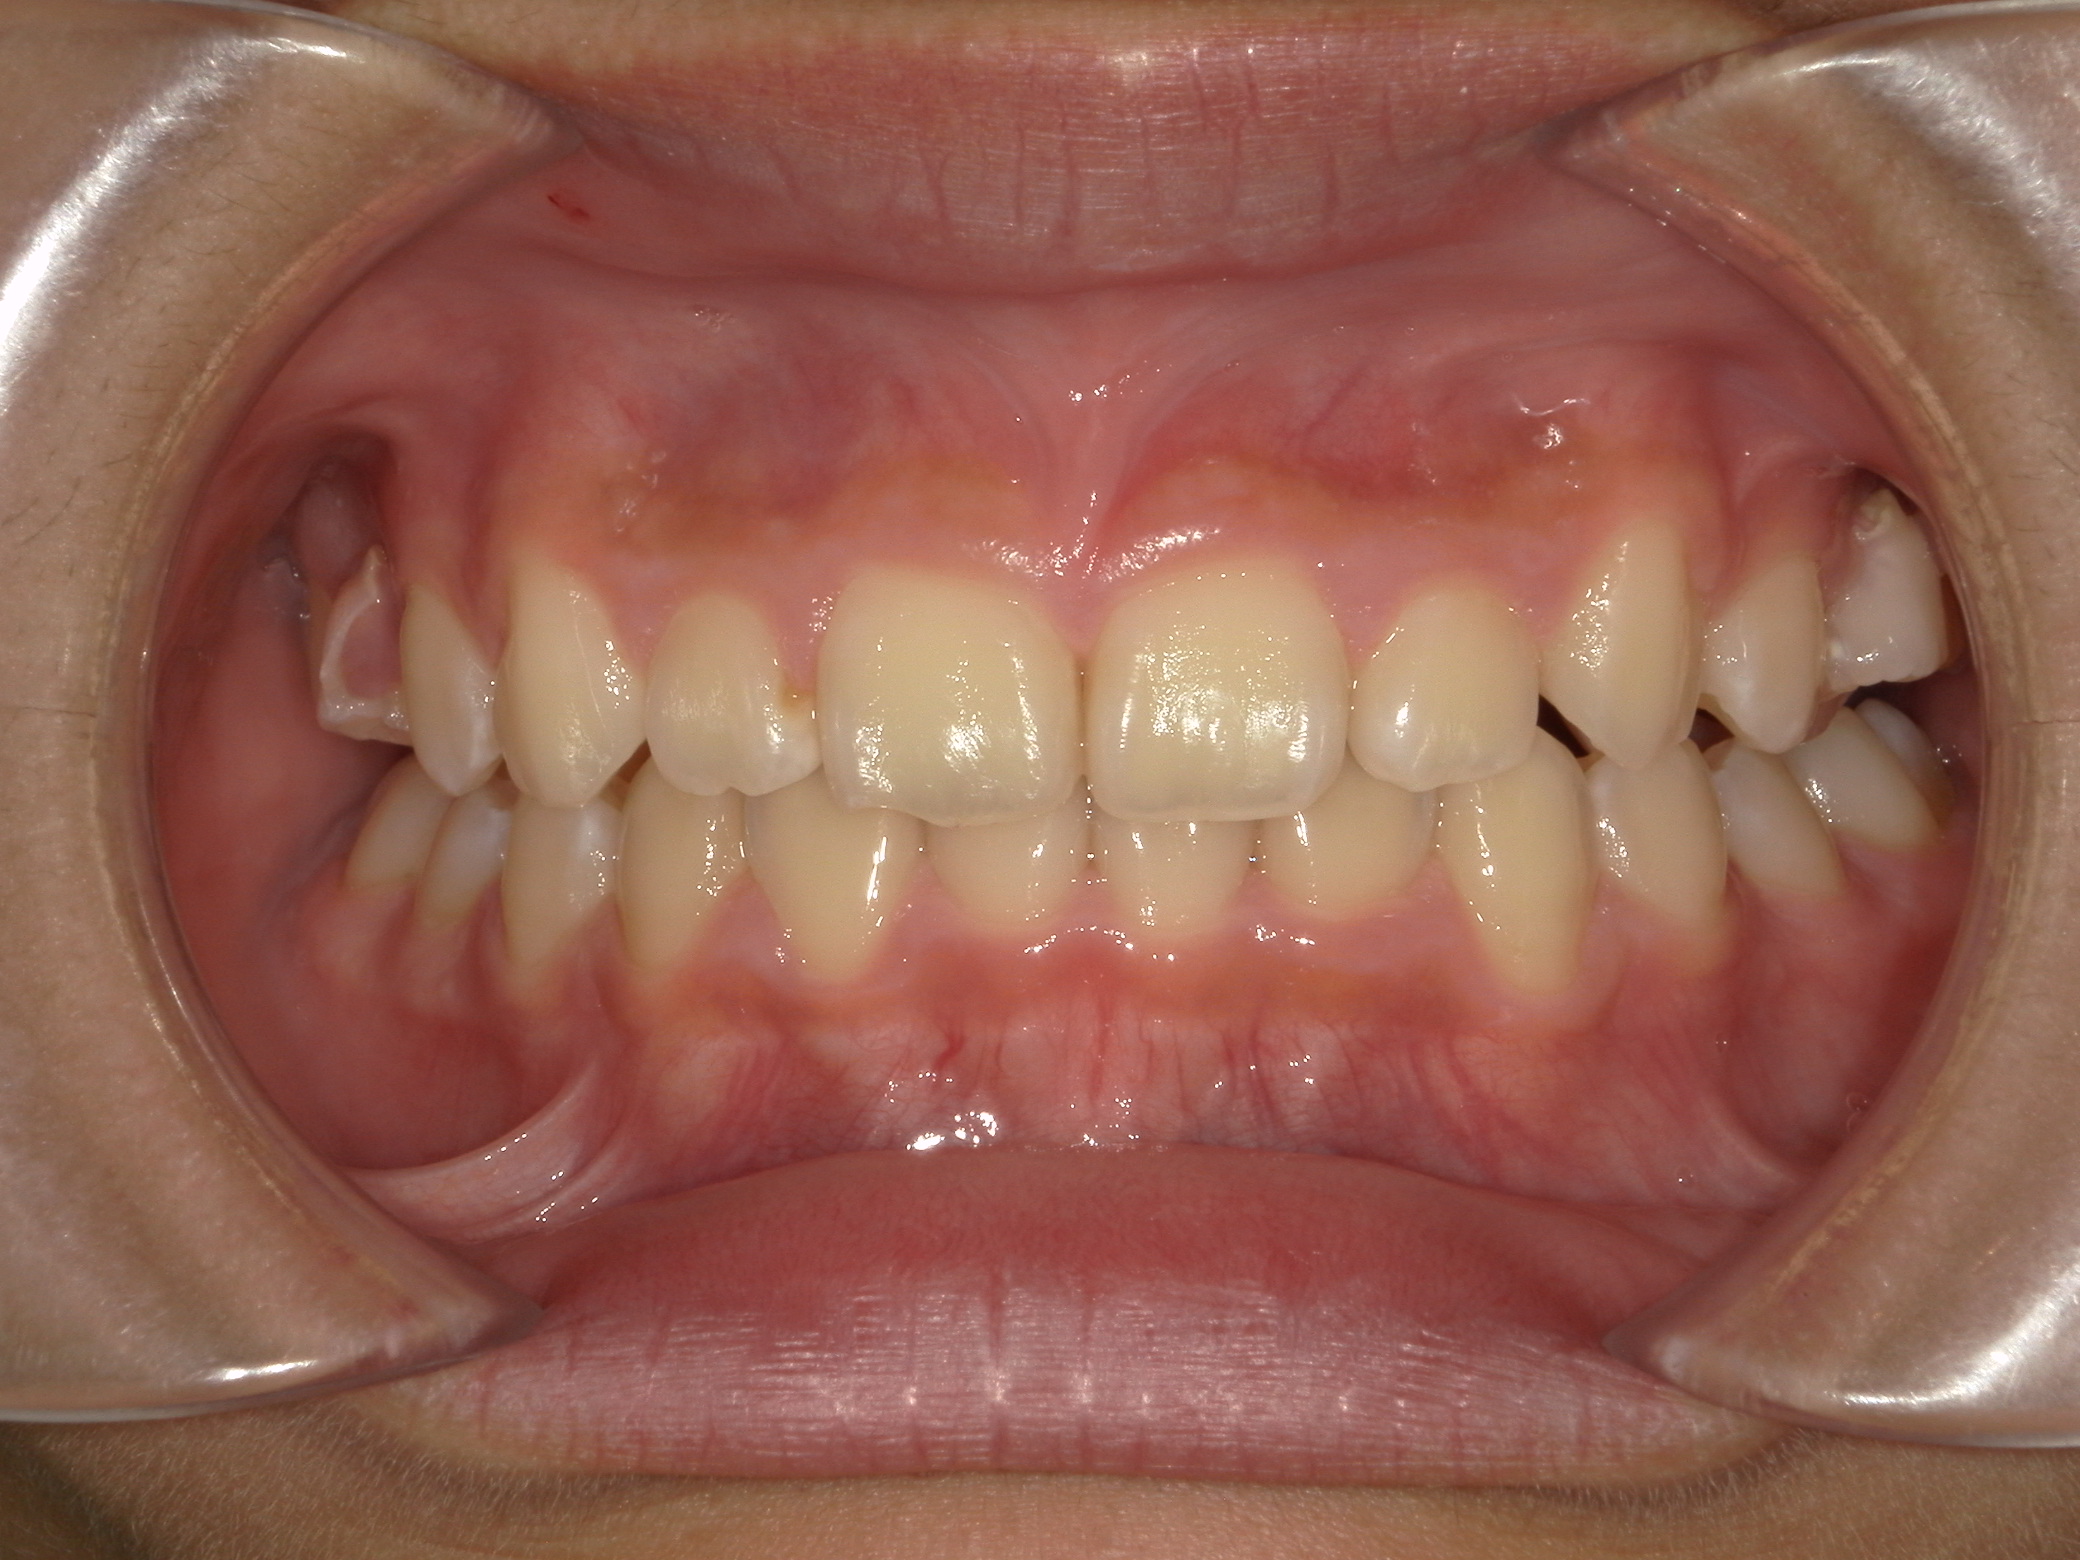

すきっ歯(11歳空隙歯列)

11歳 男性

治療例前

治療法

装置

費用

期間

付記

隙間が歯列全体にあり、かみ合わせも深い状態でした。

上下にワイヤーを装着し、かみ合わせをあげながら隙間を閉じています。

副作用:歯根吸収・歯髄壊死・歯肉退縮・隙間の再発